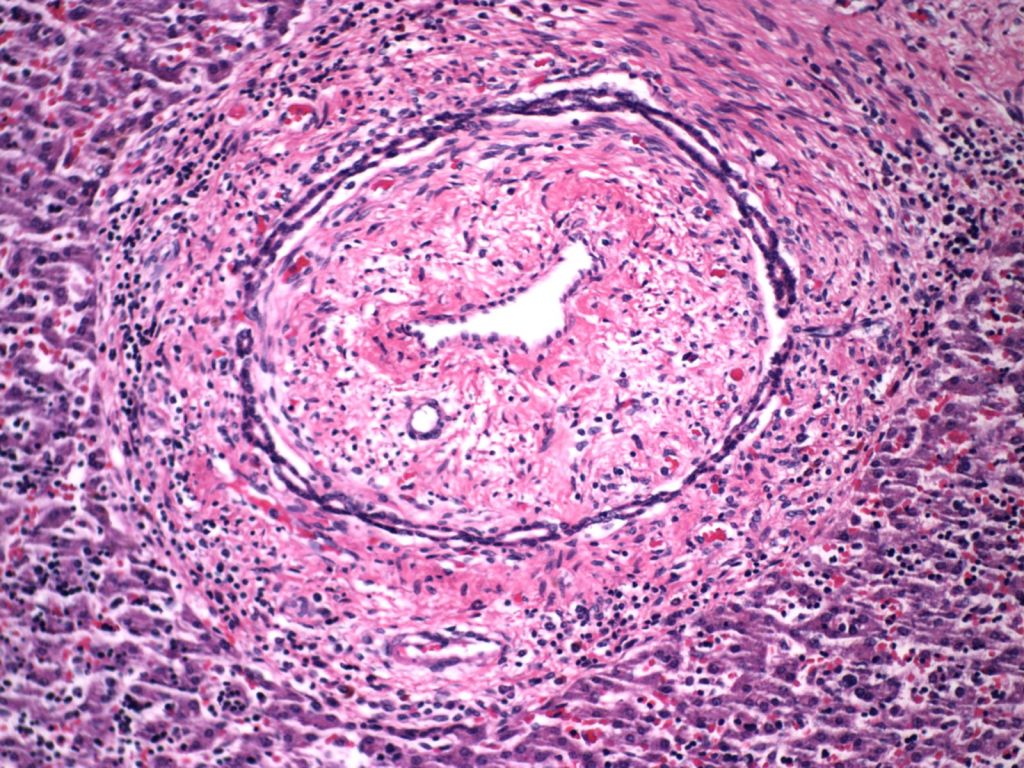

Hemorrhage and congestion: In the fetal liver, the majority of the oxygenated blood from the umbilical vein is supplied to the portal venous system but with a large portion also shunted through the ductus venosus to the inferior vena cava. With fetal hypoxia, the ductus venosus widens and more blood is shunted to the heart8. Despite this shift, in some stillbirths with fetal asphyxia, the liver shows marked sinusoidal congestion likely from a sudden increase in right heart pressure from cardiac hypoxia and poor contraction (Fig 10a, b).

Constriction of the ductus arteriosus would also be expected to suddenly increase right heart pressure and liver congestion. The sinusoidal congestion may be accompanied by periportal hemorrhage likely because the increase in right atrial pressure is also transmitted to the portal system through the ductus venosus (Fig 11).

Because of the anatomy, such periportal hemorrhage may be more prominent in the left lobe because of the attachment of the left portal vein to the ductus venosus, but this has not been systematically investigated.